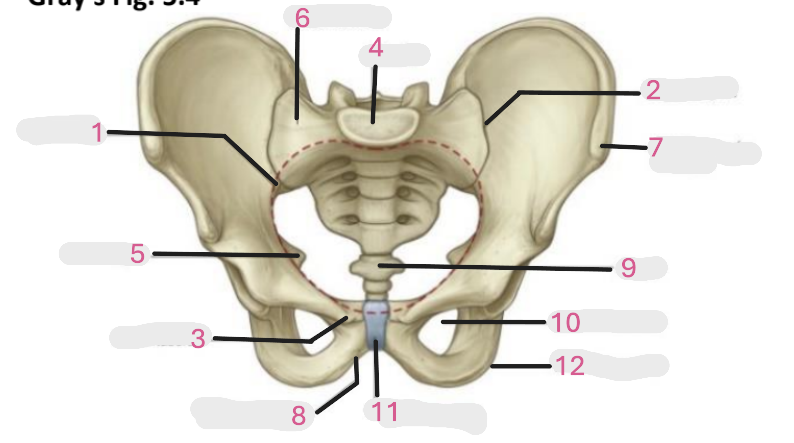

Where is the pelvic inlet

1

Where is the sacro-iliac joint

2

Where is the pubic tubercle

3

Where are the S1 body

4

Where is the ischial spine

5

Where is the ala of sacrum

6

Where is the anterior superior iliac spine

7

Where is the ischiopubic ramus

8

Where is the coccyx

9

Where is the obturator foramen

10

Where is the pubic symphysis

11

Where is the ischial tuberosity

12